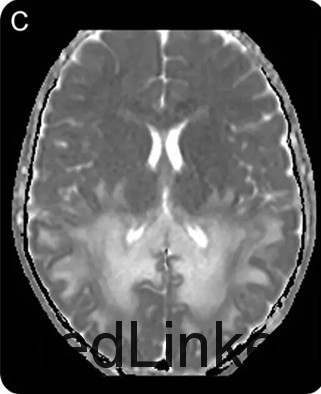

查体发现患儿皮肤色素沉着及低血压。神经系统查体提示理解困难,双眼视力下降、共轭凝视不良,辩距不良,步态不稳。脑脊液蛋白升高。头颅MRI如下图。清晨皮质醇水平降低,促肾上腺皮质激素兴奋试验证实肾上腺功能不全功能。神经遗传学检测提示ABCD1基因突变

ALD是一种先天性代谢性疾病,也是最常见的溶酶体病之一。属于X-连锁遗传病。本病特征性的影像学改变是MRI可见双侧顶枕区白质对称性分布的蝴蝶样长T1长T2信号,早期即可以胼胝体压部受累,并将两侧病灶连为一体。(神经病学俱乐部)本病一般预后较差,在出现神经症状后1~3年死亡。